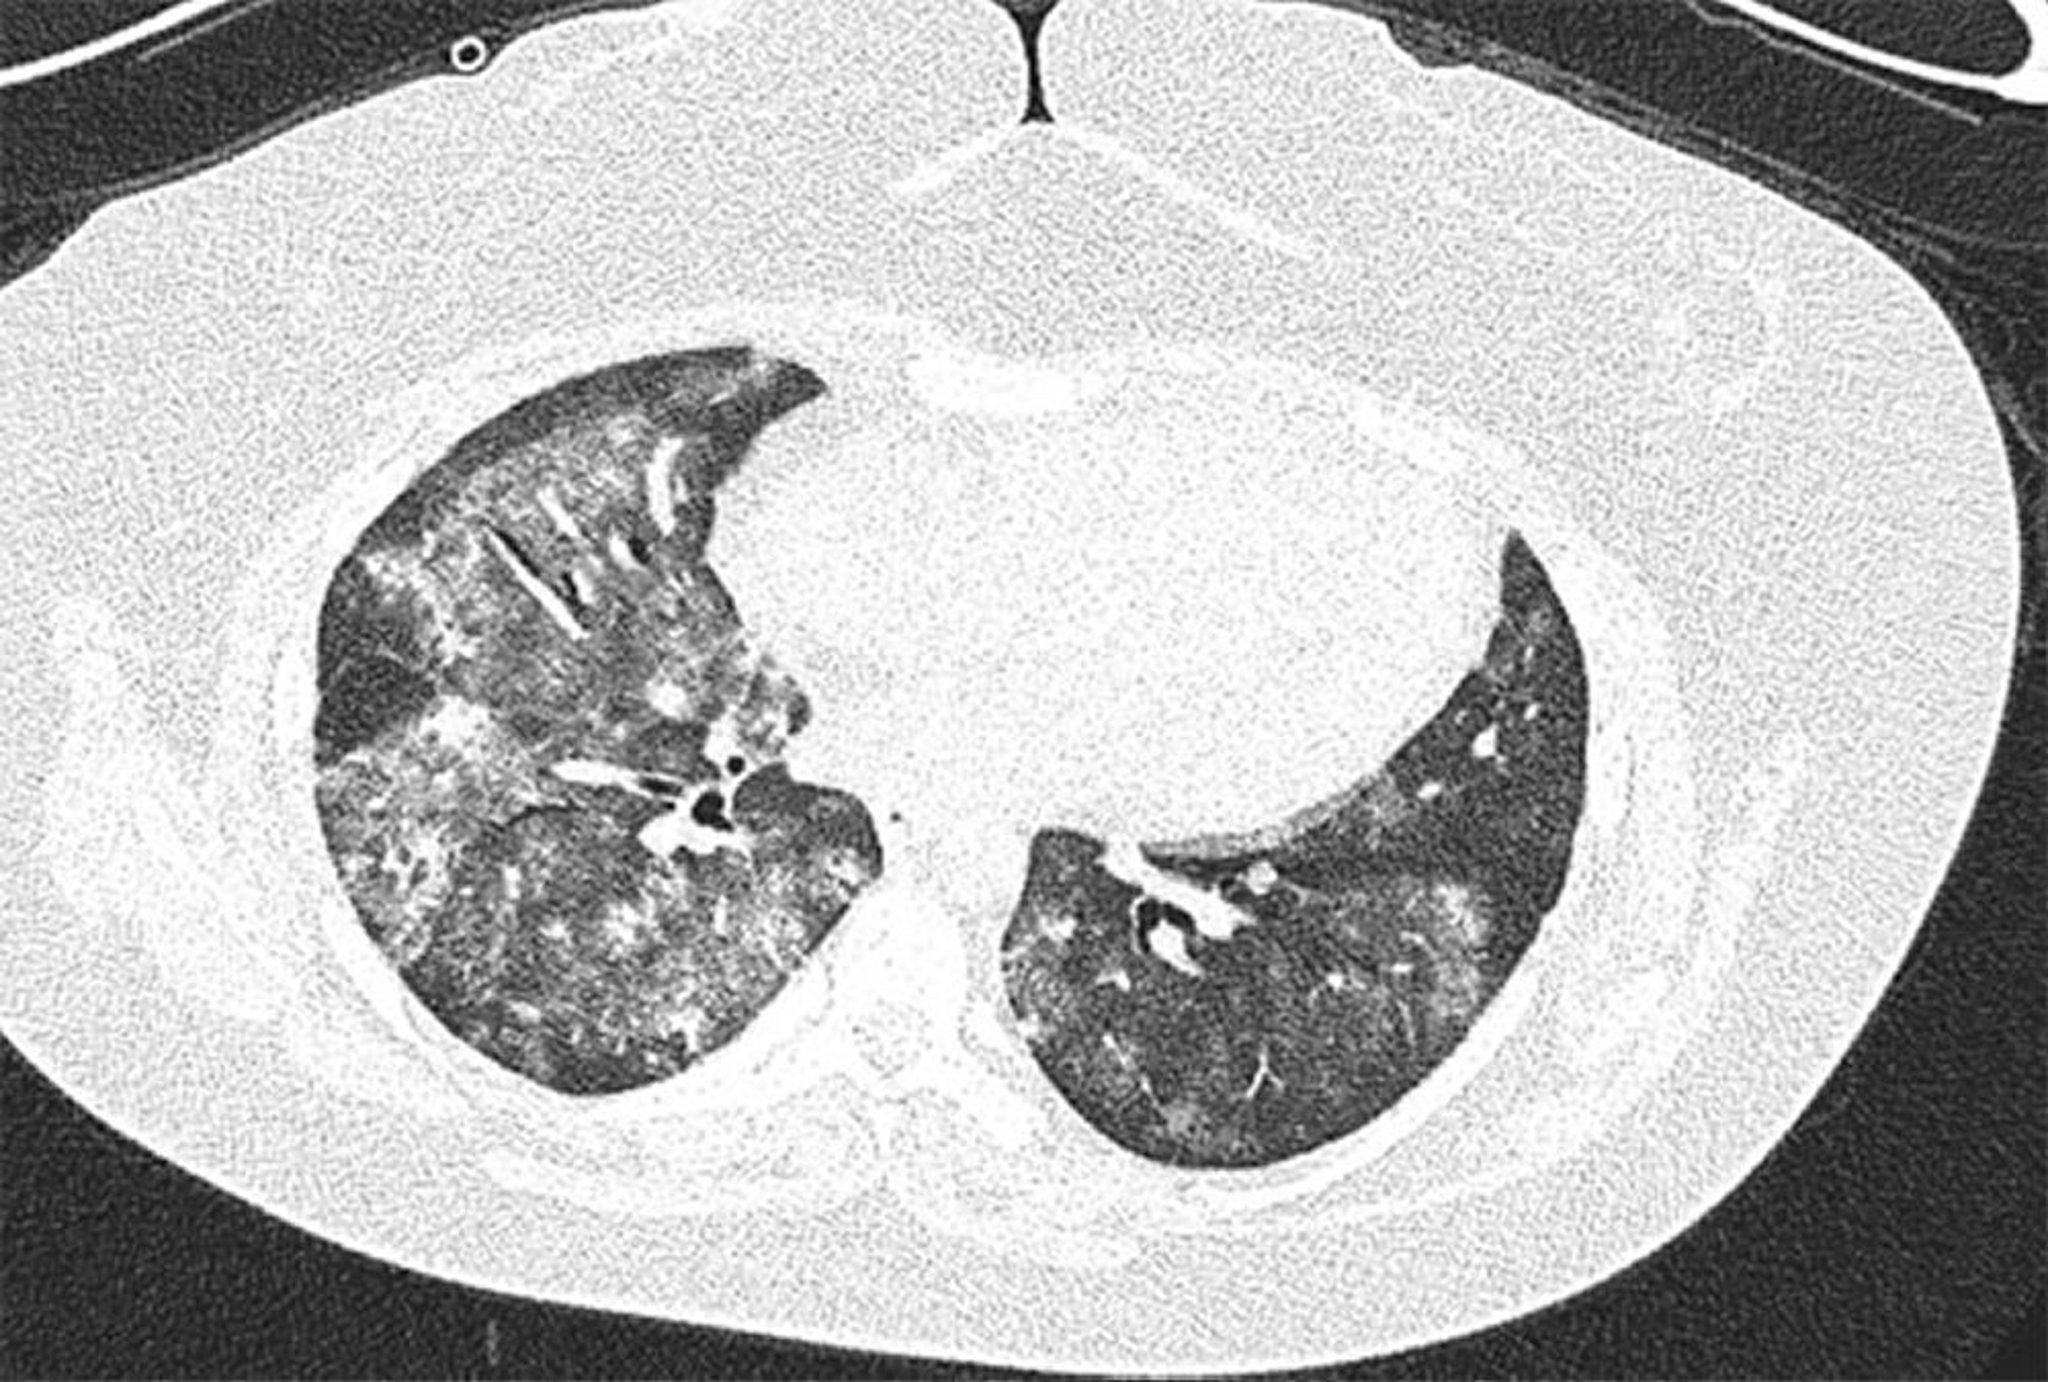

Hemorragia alveolar difusa

Imagen de TC de alta resolución de una mujer de 28 años con síndrome antifosfolipído con hemorragia alveolar difusa recurrente. La imagen muestra opacidades alveolares bilaterales y en parches de vidrio esmerilado con preservación subpleural. El lavado broncoalveolar confirmó la hemorragia alveolar.

Image courtesy of Joyce Lee, MD.